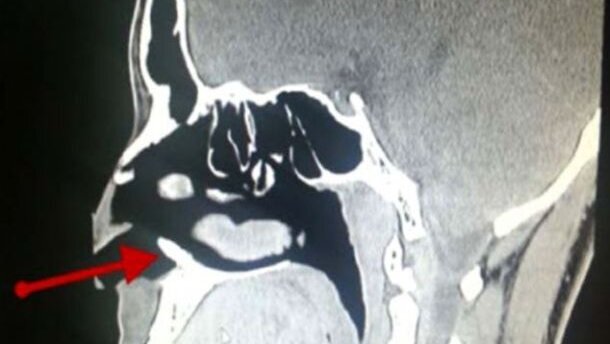

DAHRAHN, SAUDI-ARABIË – Een bloedneus komt regelmatig voor, maar een 22-jarige man in Saudi-Arabië had er wel erg vaak last van. Bijna drie jaar lang had hij één of twee bloedneuzen per maand. Artsen constateerden een wel heel bijzondere oorzaak: er groeide een tand in zijn neusholte.

Toen een arts de oorzaak van de veelvuldige neusbloedingen zocht, ontdekte hij in de neusholte een witte, benige massa van één centimeter lang. De man werd geopereerd om de massa te verwijderen, waarna de bloedneuzen niet meer terugkeerden. Een tandarts stelde vast dat het inderdaad een tand betrof die de chirurgen hadden verwijderd.

De man had wel een compleet gebit, de tand in zijn neusholte was ‘extra’. Het komt vaker voor dat mensen een overtollige tand hebben, zegt tandarts en hoogleraar Orale Pathologie John Hellstein tegen LiveScience.com. Maar deze groeien zelden helemaal door de bodem van de neusholte heen. “Het is een zeer ongewone casus, en absoluut de meest indrukwekkende intranasale foto die ik ooit heb gezien.”

Volgens Hellstein had de man waarschijnlijk een mesiodens, een veelvoorkomend type extra tand dat rond de snijtanden wordt aangetroffen. Ongeveer een derde van deze tanden ontwikkelt zich ondersteboven en kan daardoor verplaatsen naar boven, richting de neus.